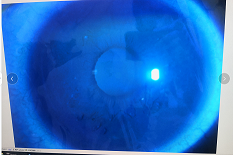

圓錐角膜要做那種治療比較好

【文章導(dǎo)讀】圓錐角膜的治療應(yīng)該依據(jù)角膜發(fā)展的時期選擇。目前圓錐角膜按照臨床癥狀大致可以分為四個時期,分別為潛伏期、初發(fā)期、完成期和瘢痕期,各個時期的主要癥狀表現(xiàn)如下: 潛伏期:

圓錐角膜的治療應(yīng)該依據(jù)角膜發(fā)展的時期選擇。目前圓錐角膜按照臨床癥狀大致可以分為四個時期,分別為潛伏期、初發(fā)期、完成期和瘢痕期,各個時期的主要癥狀表現(xiàn)如下:

潛伏期:癥狀不明顯。

初發(fā)期:開始近視,同時散光和不規(guī)則散光度數(shù)也會逐漸增加。

完成期:發(fā)展迅速,角膜明顯前突,視力銳減。

瘢痕期:角膜急性角膜水腫、混濁,消退后基質(zhì)層殘留瘢痕。

對于對于進(jìn)展非常慢,可能幾年曲率都不變化的圓錐角膜,可以觀察隨診,或者佩戴RGP矯正。如果角膜發(fā)展較快,近視散光度數(shù)增加較快,則需要通過角膜交聯(lián)來治療。

圓錐角膜的形成機(jī)制就是膠原變薄,變?nèi)?。圓錐角膜患者的角膜膠原變薄了以后,彈性增加,正常的眼壓會使角膜向前膨隆。

角膜膠原交聯(lián)手術(shù)可以通過藥物,維生素B2和紫外線交聯(lián),使角膜里面的膠原纖維的硬度增加,在對抗正常眼壓情況下,對抗力增加。交聯(lián)后角膜的韌度增加,就不容易再往前繼續(xù)發(fā)展。

但如果已經(jīng)發(fā)展到圓錐后期,再去交聯(lián)就沒有意義,就只能通過角膜移植手術(shù)治療,把向前凸起的角膜給切掉,換成新的角膜。

目前圓錐角膜的治療方式主要就是配鏡矯正、角膜膠原交聯(lián)手術(shù)以及角膜移植手術(shù)這幾種。